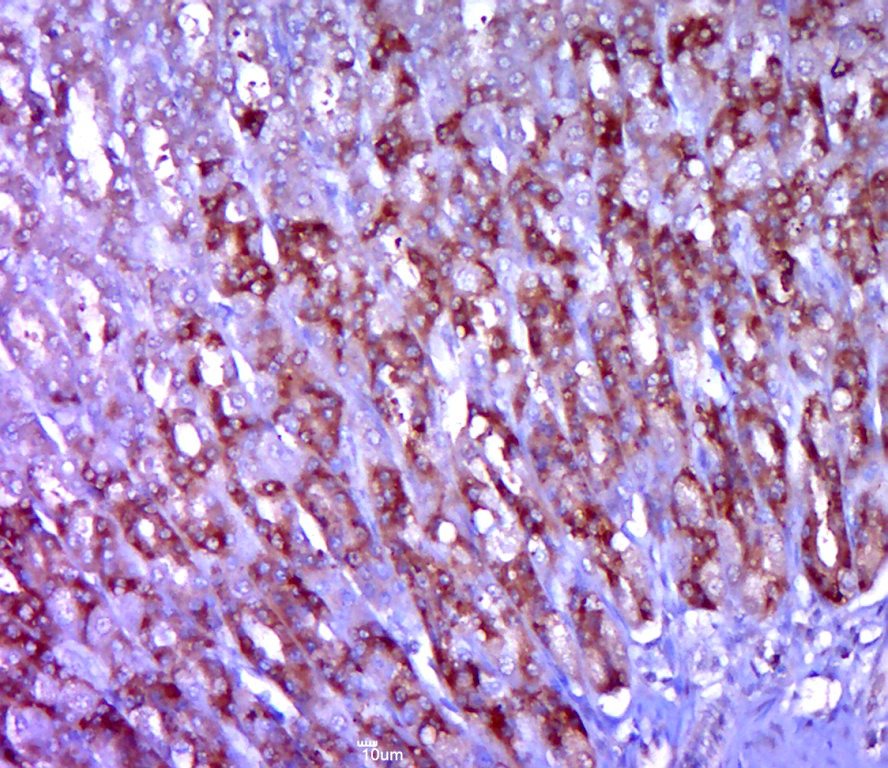

1. Tissue/cell: mouse lung tissue; 4% Paraformaldehyde-fixed and paraffin-embedded;

Antigen retrieval: citrate buffer (0.01M, pH6.0), Boiling bathing for 15 min; Block endogenous peroxidase by 3% Hydrogen peroxide for 30 min; Blocking buffer (normal goat serum) at 37°C for 20 min;

Incubation: Anti-CD28 Polyclonal Antibody, Unconjugated (TMAB-00349) 1:200, overnight at 4°C, followed by conjugation to the secondary antibody and DAb staining.

3. Paraformaldehyde-fixed, paraffin embedded (rat stomach tissue); Antigen retrieval by boiling in sodium citrate buffer (pH6.0) for 15 min; Block endogenous peroxidase by 3% hydrogen peroxide for 20 min; Blocking buffer (normal goat serum) at 37°C for 30 min; Antibody incubation with (CD28) Polyclonal Antibody, Unconjugated (TMAB-00349) at 1:400 overnight at 4°C, followed by a conjugated secondary for 20 min and DAB staining.